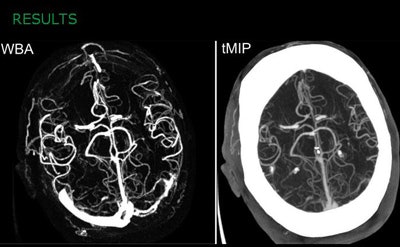

WBA method provides better contrast-to-noise ratio and is qualitatively superior to tMIP images. All images courtesy of Lukas Havla, PhD."Our proposed WBA method provides ninefold better CNR compared to tMIP," said lead study author Lukas Havla, PhD in a presentation at the RSNA 2014 congress. "It removes nonenhanced structures such as bone, and qualitative reading of WBA gives us results rated better than tMIP in five of eight categories."

The results showed a CNR for the wavelet reconstruction (580.2 ± 474.5) that was significantly higher than the tMIP approach (60.7 ± 31.0, Wilcoxon test p < 0.00001). Compared quantitatively, the new method performed significantly better than the tMIP approach, with a mean score of 3.7 (both readers), and interobserver Cohen's Κ = 1 versus tMIP scores of 2.8 Κ = 0.594 (p < 0.001).

Mean CNR is improved about ninefold with WBA method versus tMIP.In particular, small vessels that could barely be seen on tMIP images were more easily visualized on WBA images, he said. Reader confidence was improved reading WBA versus tMIP images. Qualitatively, there was no difference between the two methods in middle superimpositions or motion artifacts, Havla said.